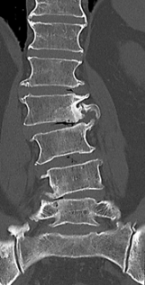

【術前】

CT検査で関節突起部に腰椎分離症を認めています。若年者の腰痛の原因となります。

【術後】

CT検査で関節突起部の骨移植を伴う分離部修復術を施行し骨癒合が得られています。